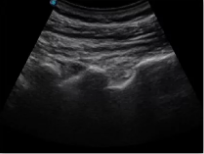

腰椎小關(guān)節(jié)